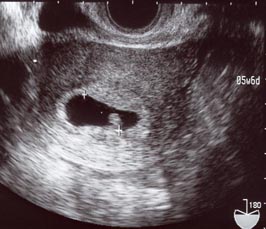

5W6d

この前(6/9)に行ったときに貰ったエコー写真は

6/16に貰ったエコー写真には5週6日と書いてある…。

これが6/16のエコー写真。

この黒い楕円の中の白い豆みたいなのが赤ちゃん。

「こっこちゃん」と呼んでおります。